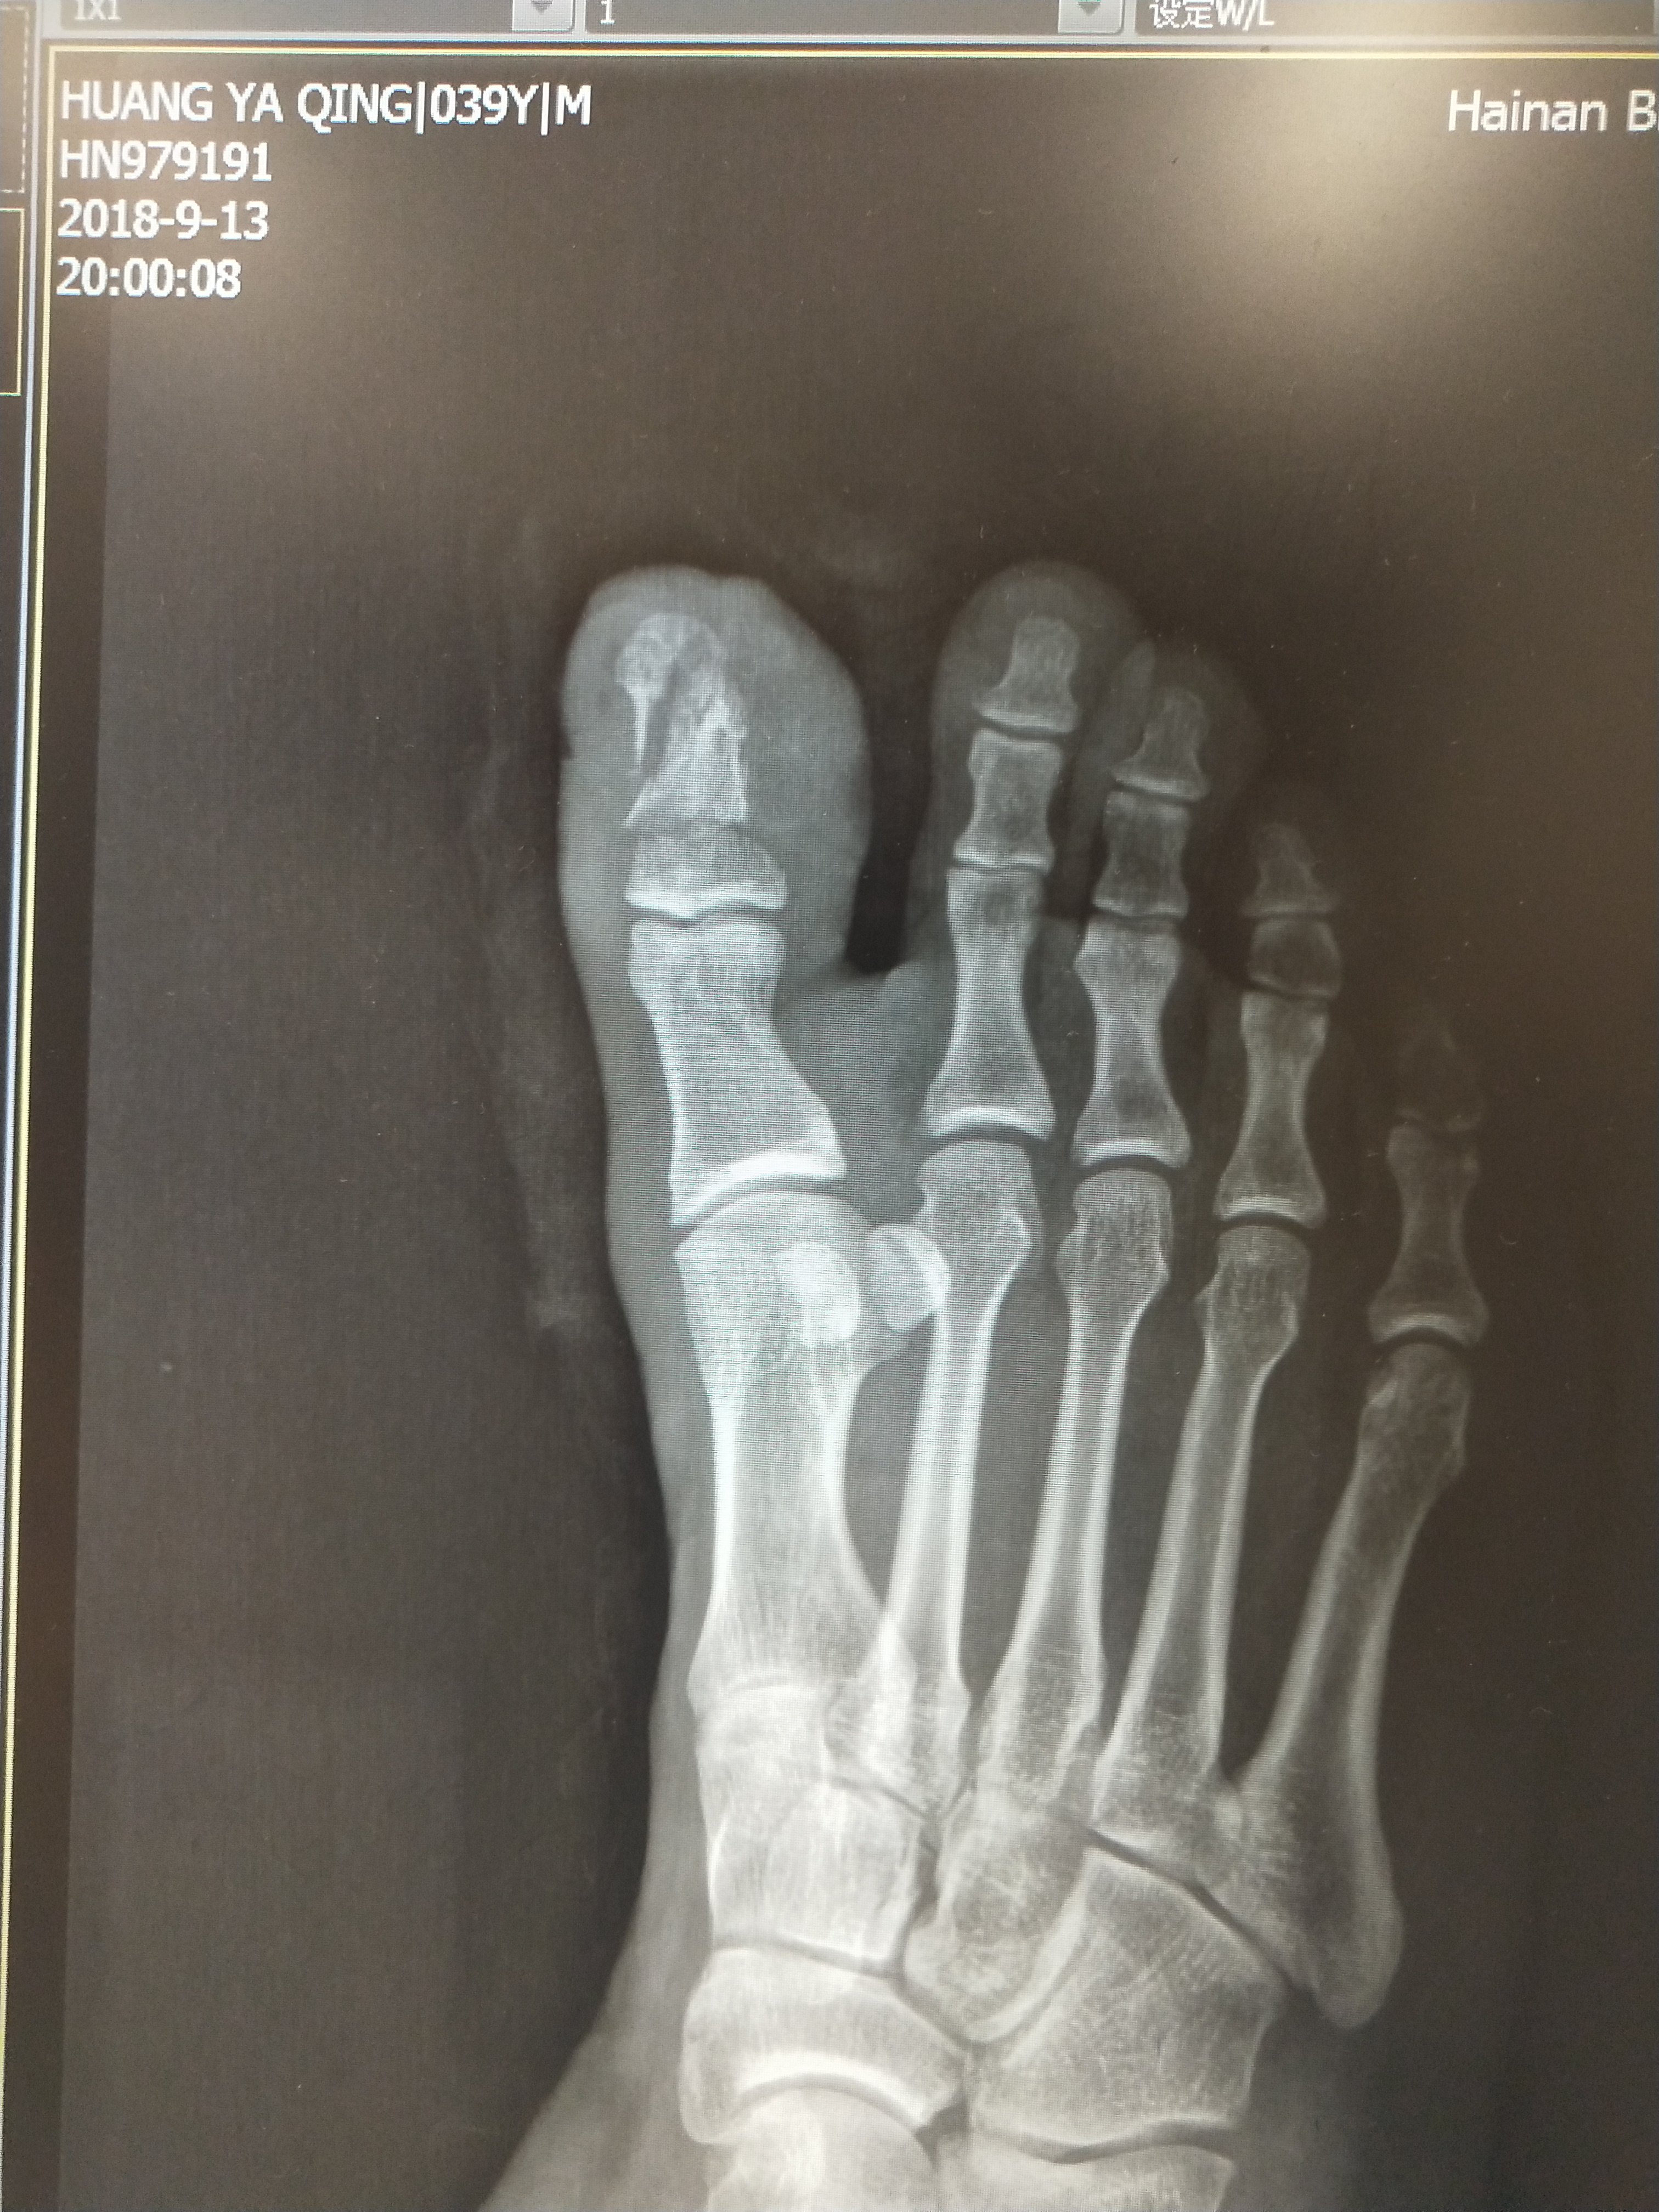

脚大拇指骨折的症状 第1页 一起扣扣网

脚大拇指骨裂图片 第1页 一起扣扣网

脚大拇趾骨折了怎么办

脚拇指骨裂图片超 第1页 一起扣扣网